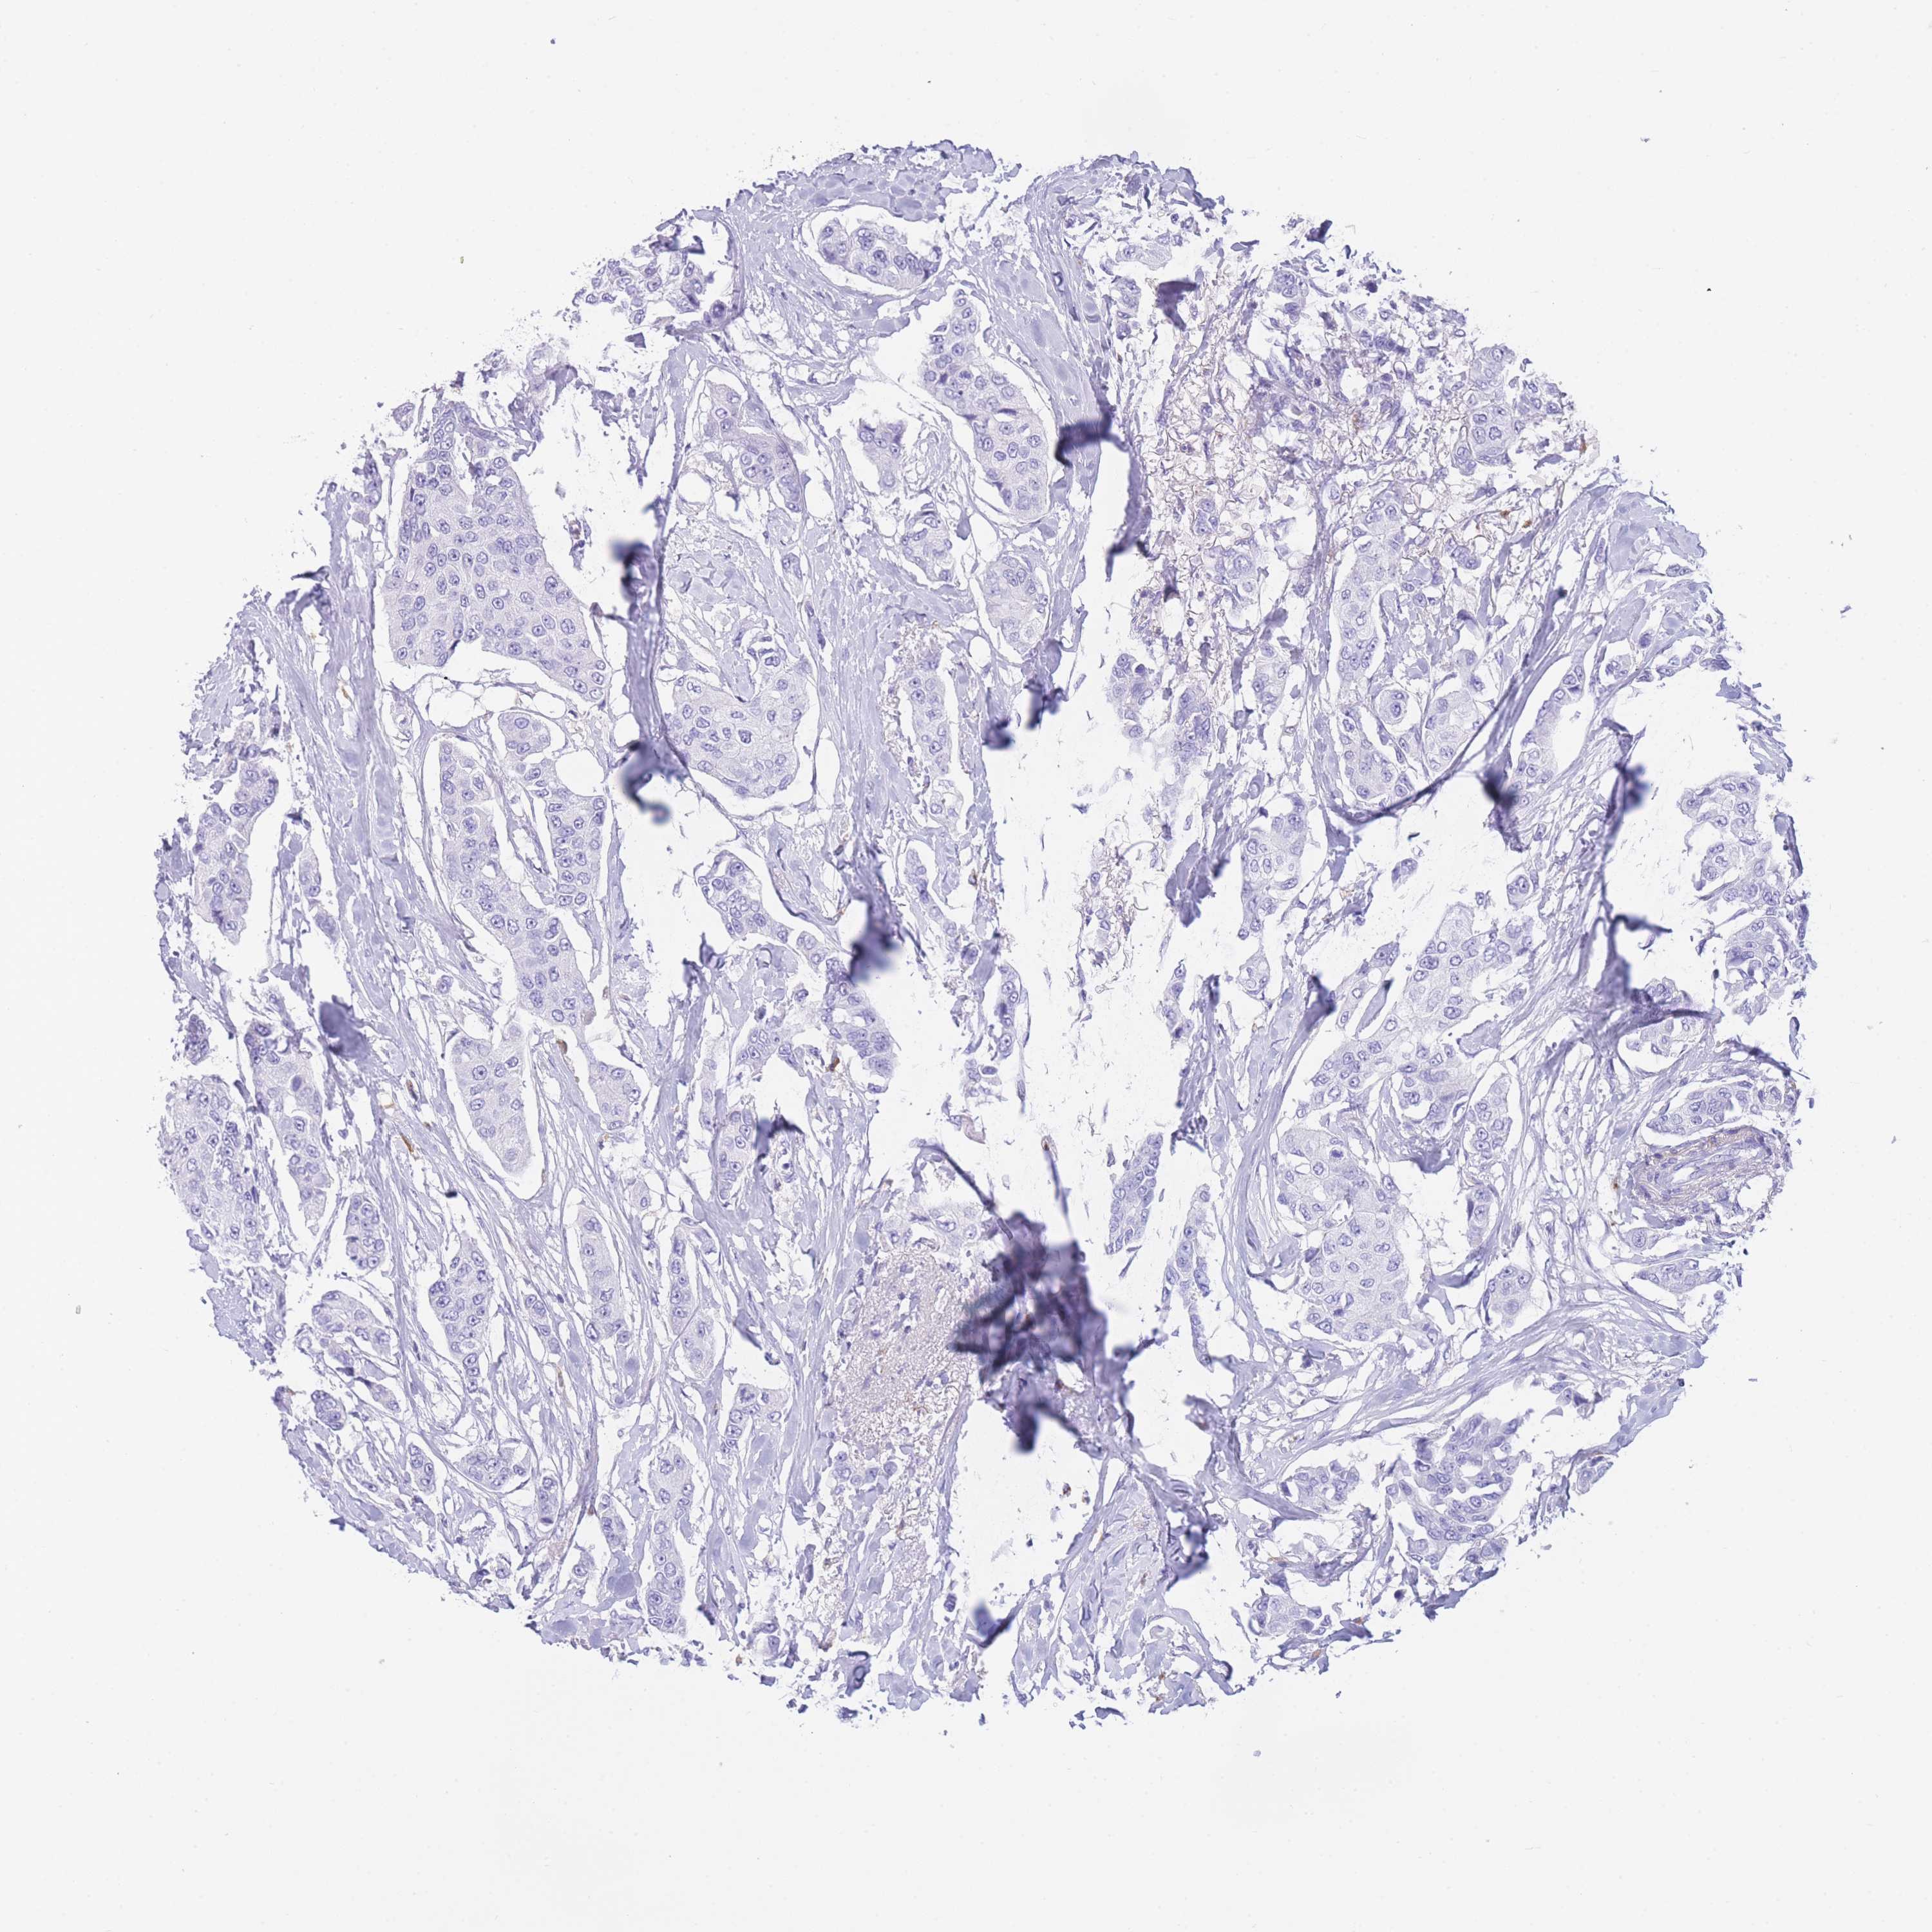

CANCER BREAST CANCER Show tissue menu

BRCA TCGA BRCA VALIDATION PROTEIN EXPRESSION